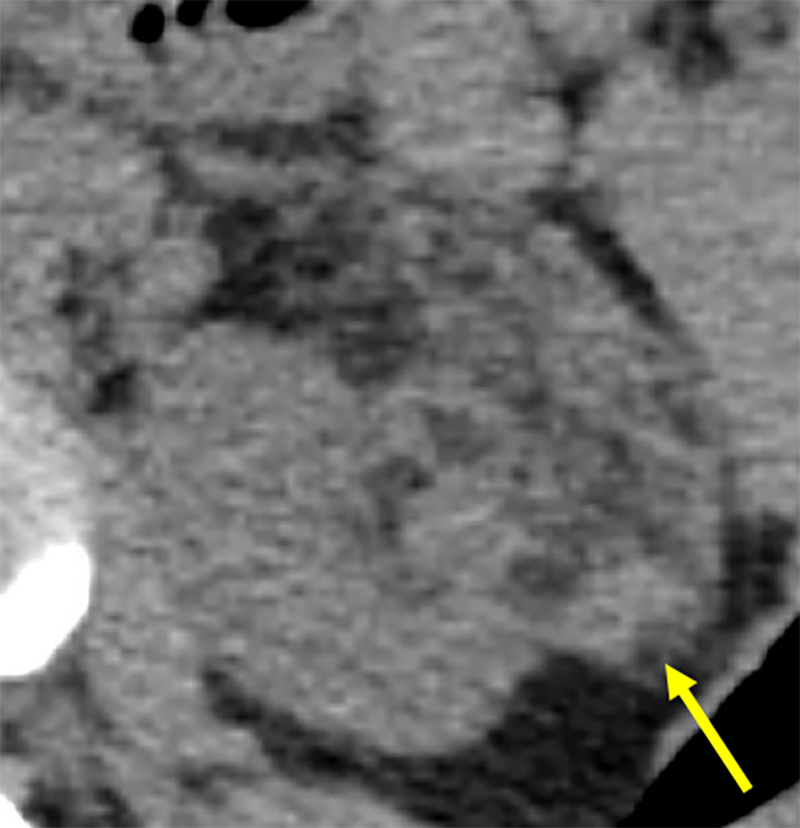

診断における造影CTの必要性は、AMLのタイプによって異なる場合がある。典型的な脂肪成分を含むclassic AMLの診断に際しては、単純CTでの脂肪濃度の検出により診断可能であり、造影CTが必ずしも必要ではない。一方、脂肪成分に乏しいfat-poor AMLの診断においては、腎細胞癌との鑑別が重要となり、造影パターンの評価が診断に不可欠である。また、正確な腫瘍径の測定、腫瘍内動脈瘤の有無、出血リスクの評価など、治療適応を判断する際にも造影CTが有用となる。

AMLと診断された場合、有症状であることは治療適応となる。具体的な症状としては、側腹部痛、腫瘤触知、肉眼的血尿などが挙げられる。無症状の場合、腫瘍径4cm以上が治療開始の一般的な指標とされている。動脈瘤径も出血リスクと関連しており、動脈瘤径5mm以上を予防的治療の適応とすることが推奨されている。ただし、結節性硬化症に伴うAMLは若年女性に多く、両側性・多発性で腫瘍径も大きい傾向があるため、散発性AMLの基準である4cmをそのまま適用することは必ずしも適切ではなく、腫瘍の増大速度、妊娠の可能性、抗凝固剤使用の有無などを含めた総合的な判断が必要となる。

本症例では術前の造影CTから左腎動脈上極枝のほか、左腎動脈本幹から分岐する左上腎被膜動脈が栄養血管として同定され、この画像情報を参考にして塞栓術が施行された。術中の血管造影においても左上腎被膜動脈が腫瘍を栄養する血管として確認され、術前の造影CT所見の通りであった。